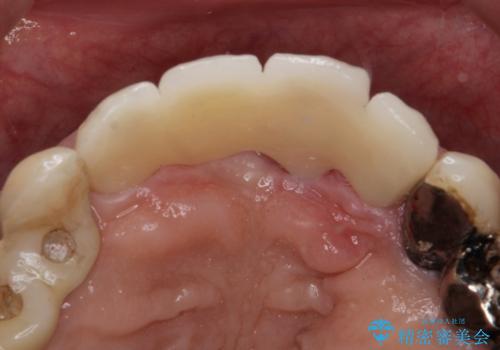

- 前歯がグラグラするとの事で来院。

精査したところ、右上の前歯はかなり動揺があり保存できない状態でした。

右上の前歯の抜歯を行い、ブリッジの仮歯を入れ、動揺が無くなるのを確認した後、ジルコニアクラウンブリッジを入れました。